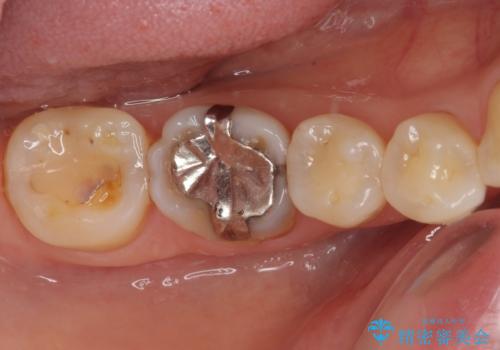

- 奥歯の銀歯をすべてゴールドにすることを希望された患者様です。

セラミックインレーによる補綴治療も提案しましたが、ご自身で強い咬合力を認識しており、歯にもインレーにもダメージの少ないゴールドインレーにて処置することとしました。